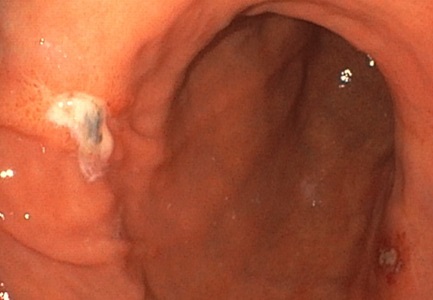

| ˆف’×ل‡(ƒsƒچƒٹ‹غٹ´گُ‚ة‚و‚é‚à‚ج) | |

| ˆف’×ل‡پAڈ\“ٌژw’°’×ل‡‚جŒ´ˆِ‚ج‘½‚‚ح ƒwƒٹƒRƒoƒNƒ^پ[ƒsƒچƒٹ‹غٹ´گُ‚ة‚و‚é‚à‚ج‚إ‚·پB ‚ـ‚½پAƒsƒچƒٹ‹غ‚جژ‘±ٹ´گُ‚حˆفٹà‚جŒ´ˆِ‚ة‚à‚ب‚è‚ـ‚·پB “–‰@‚إ‚حگد‹ة“I‚بڈœ‹غژ،—أ‚ً‚¨‚·‚·‚ك‚µ‚ؤ‚¢‚ـ‚·پB ƒsƒچƒٹ‹غ‚ج‰ًگà‚ح‚±‚؟‚ç •گ“c–ٍ•iچH‹ئ‡ٹ‚جHP‚ض‚جƒٹƒ“ƒN پ¦ƒsƒچƒٹ‹غ‚جژتگ^‚ح•گ“c–ٍ•iچH‹ئ‡ٹ‚©‚ç’¸‚«‚ـ‚µ‚½پB |